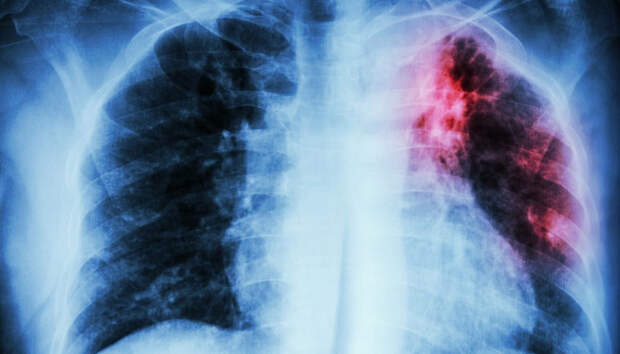

Оперштаб порадовал малым числом госпитализированных и отсутствием летальных исходов В Карелии всего семь человек за последние сутки помещены в стационар с легочной инфекцией, сообщает республиканский оперштаб по борьбе с коронавирусом. Начиная с 1 апреля 2020 года, с внебольничной пневмонией госпитализирован 5601 пациент, 130 человек умерли (с учетом пациентов, госпитализированных ранее указанного периода).